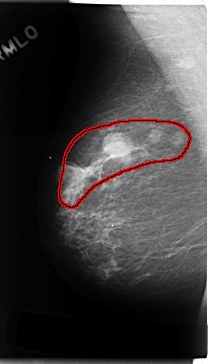

ics_version 1.0 filename C-0182-1 DATE_OF_STUDY 13 5 1996 PATIENT_AGE 62 FILM FILM_TYPE REGULAR DENSITY 1 DATE_DIGITIZED 19 3 1998 DIGITIZER LUMISYS LASER SEQUENCE LEFT_CC LINES 4792 PIXELS_PER_LINE 2648 BITS_PER_PIXEL 12 RESOLUTION 50 NON_OVERLAY LEFT_MLO LINES 4752 PIXELS_PER_LINE 2512 BITS_PER_PIXEL 12 RESOLUTION 50 NON_OVERLAY RIGHT_CC LINES 4752 PIXELS_PER_LINE 2728 BITS_PER_PIXEL 12 RESOLUTION 50 OVERLAY RIGHT_MLO LINES 4728 PIXELS_PER_LINE 2696 BITS_PER_PIXEL 12 RESOLUTION 50 OVERLAY |

FILE: C_0182_1.RIGHT_MLO.OVERLAY TOTAL_ABNORMALITIES 1 ABNORMALITY 1 LESION_TYPE MASS SHAPE LOBULATED MARGINS CIRCUMSCRIBED ASSESSMENT 5 SUBTLETY 5 PATHOLOGY MALIGNANT TOTAL_OUTLINES 1 BOUNDARY |